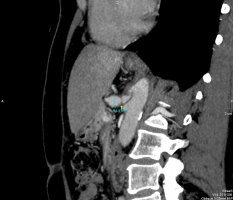

Ucisk więzadła łukowatego na pień trzewny jest przyczyną rozwoju zespołu MALS (median arcuate ligament syndrome, zespół Dunbara), objawiającego się silnym poposiłkowym bólem brzucha, mogącym prowadzić do poważnych powikłań w tym niedożywienia oraz tętniakowatego poszerzenia naczyń trzewnych. Technicznie operacja polega na przecięciu pasma łącznotkankowego uciskającego pień trzewny (tętnicę śledzionową, żołądkową lewą oraz wątrobową właściwą) przy ujściu od aorty brzusznej. Wyżej wymienione naczynia odpowiadają za prawidłowe ukrwienie większości narządów jamy brzusznej, ich uszkodzenie w kilka sekund może prowadzić do zagrażającego życiu krwawienia. Dotychczas ten rodzaj zabiegu chirurgicznego był przeprowadzany sposobem klasycznym, czyli laparotomią. Dostęp minimalnie inwazyjny pozwala na zmniejszenie urazu okołooperacyjnego, uzyskiwany jest poprzez 4 trokary (2x10mm, 2x5mm). Zastosowanie techniki laparoskopowej pozwala na szybszy powrót chorego do zdrowia, zmniejszenie pooperacyjnych dolegliwości bólowych, mniejsze ryzyko wystąpienia odległy powikłań pooperacyjnych w postaci zrostów wewnątrzotrzewnowych (mogących prowadzić między innymi do niedrożności mechanicznej przewodu pokarmowego) oraz pozostawia lepszy efekt kosmetyczny. Przeprowadzenie zabiegu sposobem laparoskopowym umożliwiło wypis ze szpitala 67. letniej pacjentki już w pierwszej dobie po operacji z zaleceniami dalszej opieki pod kontrolą przyklinicznej Poradni Chirurgicznej.

Diagnostyka obrazowa (tomografia komputerowa) – dr n. med. Adam Łukasiewicz